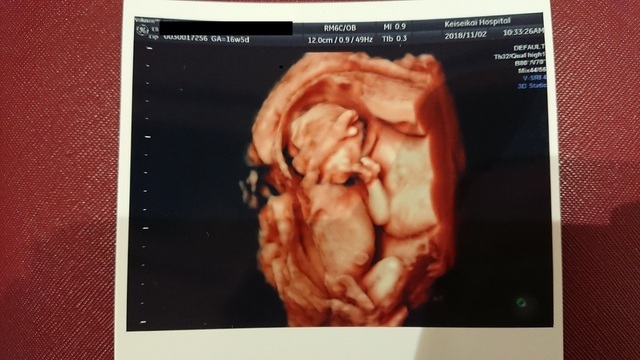

16週0日(16w0d・男の子)|うたた さん(38歳)

エコー写真撮影時のエピソード:

安定期に入って初めての4Dエコー。カラーの立体で見えて、今までエイリアンで見えていた我が子がとてもとてもかわいく感じました。

恥ずかしがってか?顔は見せてくれませんでしたが、全身が写った貴重な1枚です。